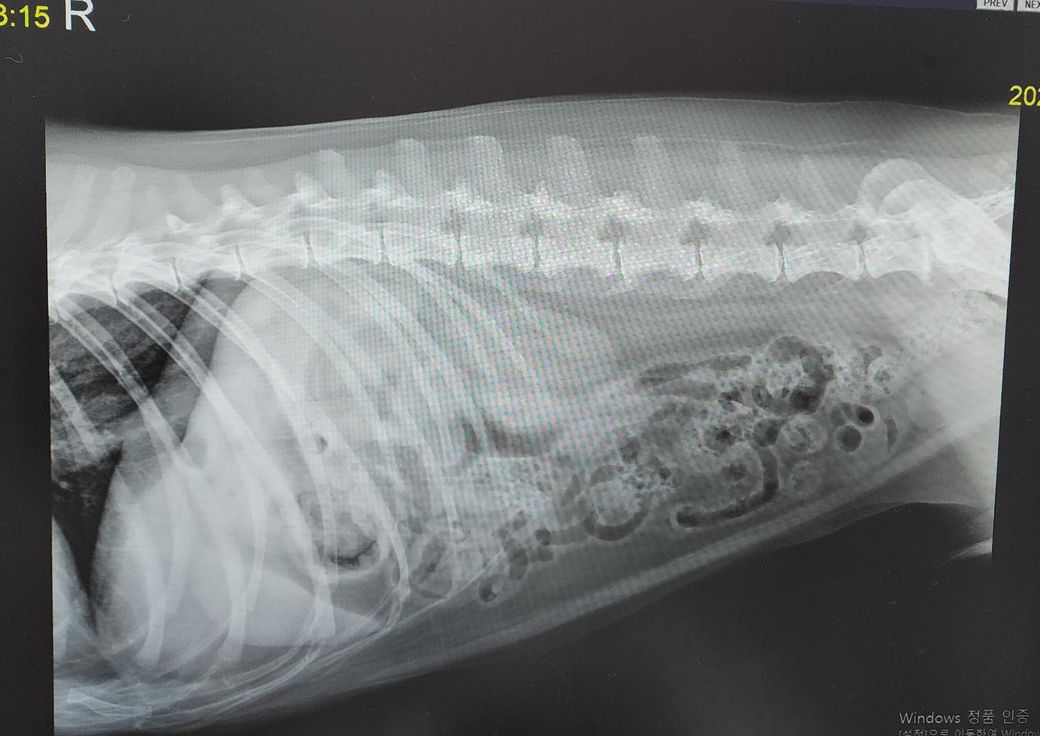

시베리안 허스키 20kg 11살 중성화 수컷 반려 중입니다.

방사선 상으로 간이 작게 나와서 주치의 선생님께서 소간증일 가능성이 있다고 하셨으나 확진은 아니었구요,

혈액검사 뇨검사 등 대부분의 건강검진을 하였으나 간과 관련된 이상증상은 없었습니다.

간이 작지 않습니다. 11살이면 노령성 위축이 있어 약간 작아야 하는데 방사선 사진상에서는 정상 크기 지표에 해당하여 상대적으로 오히려 커진 상태를 의심해야 합니다. 특히 간의 끝단이 둥근 양상으로 관찰되어 간종대가 오히려 의심됩니다. 영상전공자의 판독을 받아 보는걸 추천합니다.